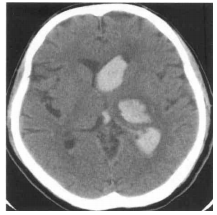

77 年約 60 歲女性路倒病人,送到急診室時意識不清,無法問取病史,根據 CT 影像(如圖),最適 當的診斷是:

(A) Hypertensive hemorrhage with extension into the ventricle (B) Contusion hemorrhage and traumatic intraventricular hemorrhage(IVH) (C) Ruptured aneurysm with intracerebral hemorrhage and IVH (D) Ruptured AVM(arteriovenous malformation)with intracerebral hemorrhage and IVH